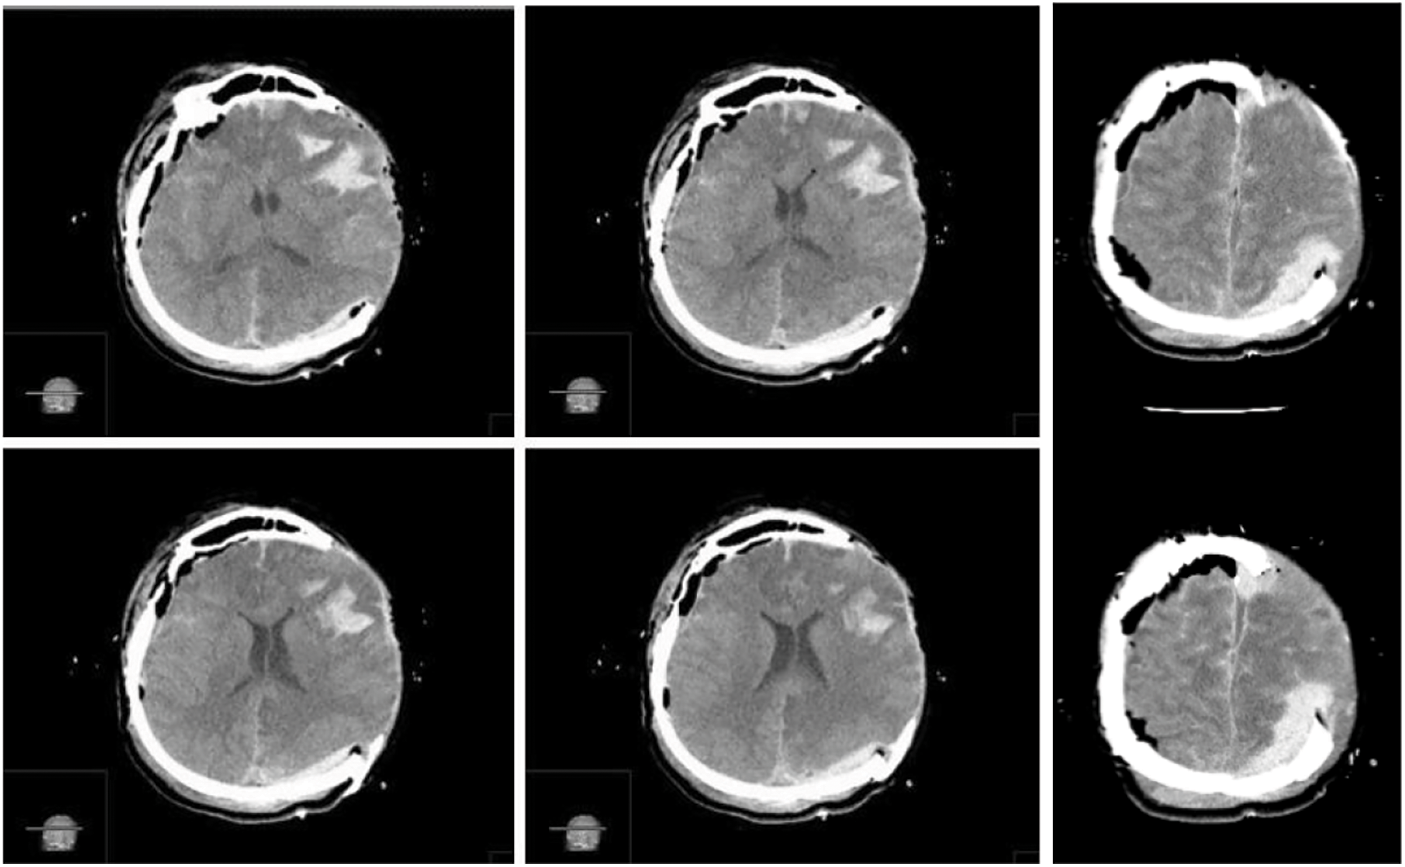

A left decompressive craniectomy was performed, and a substantial epidural blood collection was removed. Once the dura mater was opened, a concomitant massive acute SDH was detected and removed. During surgery, the brain showed progressive swelling, which made replacing the bone flap impossible. We performed a duroplasty and skin closure, as usual, along with a subgaleal drain. Due to the patient’s right anisocoria, an urgent postoperative CT scan was needed, which revealed a massive blood collection in the right hemisphere, with left midline shift (Fig. 4).

Figure 4: Immediate post-operative brain CT scan images in series revealing a massive concomitant right hemispheric acute extra-subdural hematoma, with left midline shift. In this case the “CT comma sign” and the detached dura are visible in the axial sequences (Yellow asterisks)

We completed the procedure with satisfying hemostasis, duroplasty, and repositioning of the bone flap; also in this case, a subgaleal drain was placed. After surgery, the patient was isochoric again, and a further postoperative CT scan revealed common postoperative findings and a proper brain decompression (Fig. 6).

Figure 6: Postoperative CT scan images in series showing common postoperative findings and a bilateral proper brain decompression